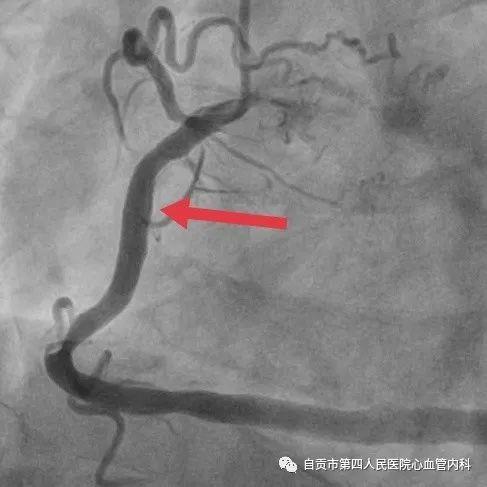

作者:汤勇 自贡市第四人民医院心血管内科引进又一利器“冠脉内超声检查(IVUS)”,助力冠心病精准治疗,目前我国冠心病发病率呈现一个高发的态势,冠心病的发病年龄也呈年轻化的趋势,20-30岁的人群发生急性心肌梗死也不少见。 ![]() 冠脉完全闭塞导致心梗 ![]() 急诊手术成功开通血管 药物加冠脉支架治疗是治疗冠心病的常规治疗手段,我们通常选择冠脉造影对患者的冠状动脉血管检查,由于冠脉造影显示的血管图像是二维图像,并不能完全真实地反映患者冠脉病变的实际情况,有可能造成不必要的支架植入,判断支架的大小完全依赖经验与造影图像,也有可能造成支架大小,长度选择不当。 ![]() ![]() 为了更精准对冠心病患者治疗,优化支架植入,减少支架植入的并发症的发生。 ![]() IVUS图像 ![]() 造影显示需要支架治疗 我院引进了美国波科公司的冠脉内超声检查(IVUS)检查设备,对患者的冠状动脉进行实时检查,为临床医生在对冠心病患者是否需要支架治疗,支架合理应用提供更为准确得信息。 ![]() 我们有一位患者在西昌某院因心肌梗死,行右冠状动脉支架治疗,当时冠脉造影检查提示右冠状动脉支架有一重度狭窄,建议择期再行支架治疗,患者慕名来我院来进一步检查。从冠脉造影的情况确实需要进行支架治疗,由于患者年轻,已安置支架4枚,故决定对患者进行冠脉内超声检查(IVUS)检查。 ![]() 支架局部膨胀不全 ![]() 冠脉内超声检查(IVUS) ![]() 支架直径恢复正常 患者冠脉内超声结果提示管腔面积能够满足心肌血供,且病变邻近血管直径大于5mm,不适合支架治疗。故建议其药物治疗,必要时复查造影。另外该患者造影显示已安置的支架显示膨胀不全的可能,进行冠脉内超声检查后显示支架内有明显膨胀不全的征象,故予以球囊扩张,支架管腔直径恢复正常。 在今后的冠心病治疗上,冠脉超声检查将发挥更大的作用,特别是复杂病变,左主干病变,钙化病变,闭塞病变方面,将大大减少冠脉介入治疗的并发症,再次支架治疗的发生率降低,将大大提高我院冠心病的精准治疗水平。 ![]() ![]() |